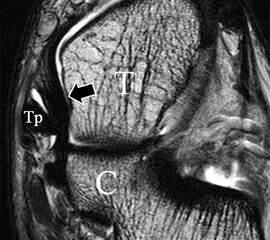

Innenbandapparat

Man unterscheidet bei dem Ligamentum deltoideum eine tiefe Schicht (Pars tibiotalare posterior, Pars tibiotalare anterius) und eine oberflächliche Schicht (Pars tibionaviculare, Pars tibiocalcaneare, Pars tibiotalare posterius superficialis und Tibiospring-Ligament) 10. Hochauflösende Techniken lassen eine differenzierte Beurteilung aller Bandanteile zu. Sowohl rein ligamentäre als auch osteo-ligamentäre Ausrisse sind normalerweise gut zu erkennen. Die Pars tibiotalaris posterior ist multifaszikulär aufgebaut und sowohl axial als auch coronar (Abb. 19 a) gut bildgebend abzugrenzen. Die deutlich kleinere, nur inkonstant angelegte Pars tibiotalare anterior inseriert an einem kleinen Talustuberkel (Abb. 19 b). Ossäre Bandausrisse kommen hier gehäuft vor. Proximal verlaufen die Pars tibiocalcaneare und die Pars tibionaviculare gemeinsam (Abb. 19 c) nach kaudal und trennen sich dann in zum Calcaneus und zum Os naviculare ziehende Bündel auf. Ein besonderer Typ ligamentärer Verbindungen stellt das Tibiospring-Ligament dar. Es verbindet nicht wie für Ligamente typisch zwei Knochen miteinander, sondern es hat seinen ossären Ursprung an der Tibia und inseriert am Pfannenband (Ligamentum calcaneonaviculare plantare, im englischen Schrifttum Spring-Ligament genannt), also nicht ossär. Das Innenband ist mit 60% der Verletzungen am häufigsten betroffen. Isolierte Innenbandverletzungen sind jedoch selten. Sie treten gehäuft assoziiert mit Syndesmosenläsionen, Fibulafrakturen, Verletzungen des Muskulus tibialis posterior und des Pfannenbandes auf (H.-K. Beyer 2003). Entsprechend sollte auf diese Kollateralverletzungen bei der Beurteilung geachtet werden. Eine weitere Folge von Verletzungen des Ligamentum deltoideum ist die chronische Sprunggelenksinstabilität. Arthroskopisch weisen hier bis zu 40% der Patienten einen elongierten Verlauf des Ligamentum deltoideum auf. In diesem Patientenkollektiv besteht auch eine erhöhte chondrale Komorbidität mit arthroskopisch erkennbaren Knorpelschäden (98%) im Gegensatz zu der Patientengruppe (66% Knorpelschäden) mit reiner Außenbandinstabilität 11. Dies belegt die klinische Bedeutung von Innenbandverletzungen.